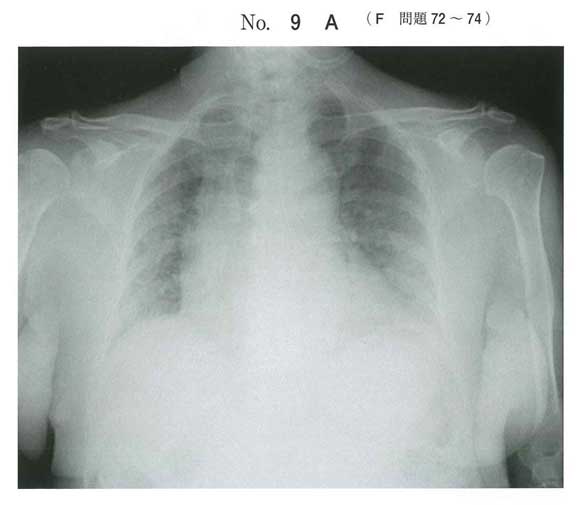

| 73 | 119F-73 | 4 | |